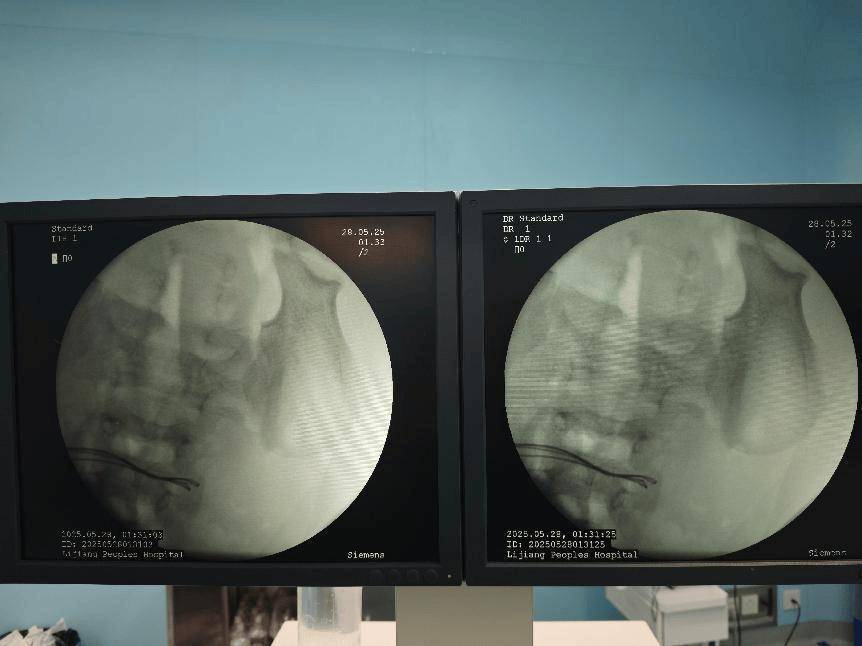

经过初步的影像学检查,医疗团队发现:病人体内竟然有37颗异物,连在一起呈手串状,并伴有小肠穿孔。

术前腹部DR片

术中完善床旁DR见腹腔内已无异物